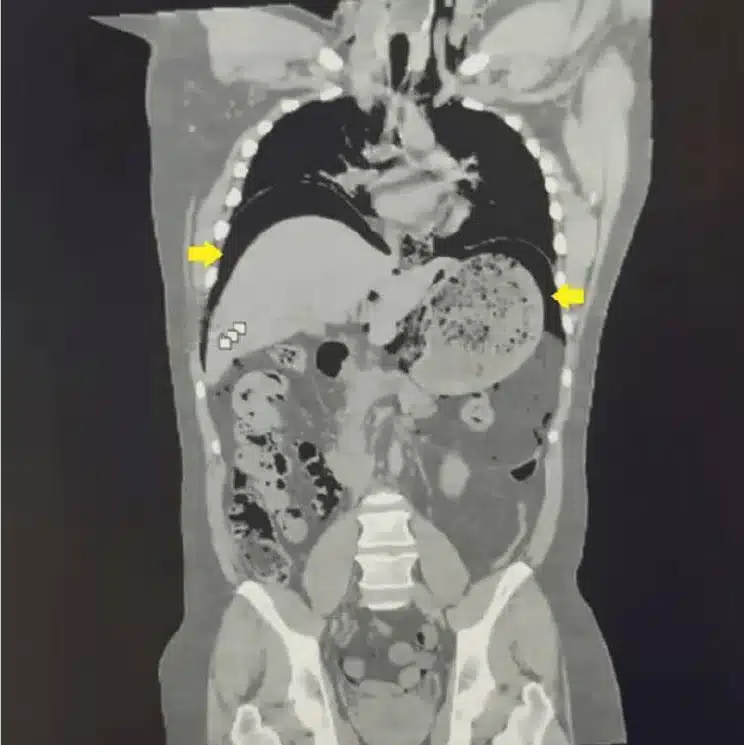

To confirm the diagnosis, doctors ordered a computed tomography scan. The imaging revealed a large amount of gas trapped inside the abdominal cavity. This condition, known as pneumoperitoneum, indicated that gas had escaped from the digestive system.

The scan also confirmed a rupture in the stomach wall. Surgeons later identified a perforation measuring roughly three centimetres. Doctors moved quickly to treat the injury.